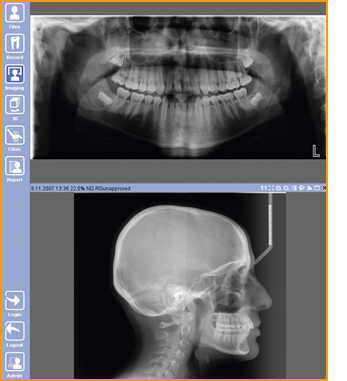

Notre unit Planmeca ProMax® 3D Classic est conçu pour obtenir des informations complètes et détaillées sur l'anatomie du patient. Cet unit à rayons X intelligent à usage multiple permet d'obtenir des radiographies panoramiques numériques, céphalométriques et 3D, ainsi que des photos 3D et des scans de modèles.

Romexis, le logiciel dédié à la dentisterie de Planmeca, intègre une multitude d'outils permettant de répondre aux besoins, à la fois, de l'imagerie, du suivi de traitement, de la gestion des patients et des unités dentaires. Sa grande convivialité lui permet de s'adapter aussi bien aux cabinets uni-poste qu'aux cabinets de groupes, centres des soins hospitalo-universitaires ou aux grandes structures hospitalières. Planmeca Romexis est compatible avec de multiples modalités d'imagerie afin de mieux gérer les procédures à rayons X, en 3D et photographiques. Toutes les images sont stockées et traitées dans un même système. Planmeca Romexis est cependant bien plus qu'un simple logiciel d'imagerie. En effet, il intègre l'imagerie numérique au sein des logiciels de gestion, il participe aux fonctionnalités des unités dentaires, ainsi qu'à d'autres postes de la clinique. Le logiciel se compose de différents modules que vous êtes libre de choisir pour mieux répondre à vos besoins.